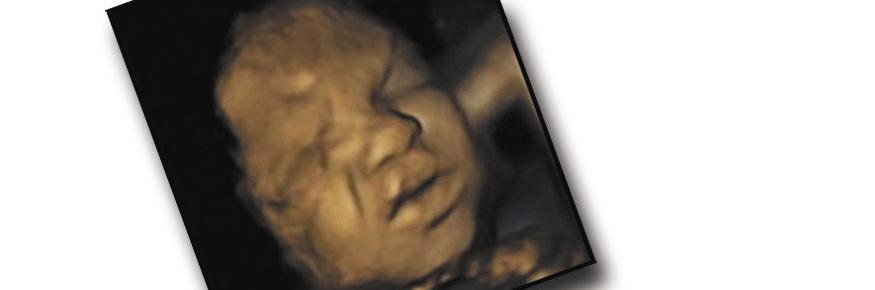

The 4D scans of 15 healthy foetuses showed that they develop from making very simple one-dimensional expressions at 24 weeks, such as moving their lips in order to form a “smile”, to complex multi-dimensional expressions which can be recognised as “pain” expressions, by the time the mother is 36 weeks into her pregnancy.

The researchers used the video footage of 4D scans, observing repeatedly the facial expressions of eight female and seven male foetuses from the second to third trimester (24 to 36 weeks) of pregnancy.

Foetuses observed at 24 weeks gestation rarely showed a combination of facial movements which make up a ‘pain face’, such as lowering the eyebrows, wrinkling the nose and stretching the mouth. However, by 36 weeks gestation, a combination of at least four movements was seen rather more frequently, giving the impression that these older foetuses were capable of making a pain face.